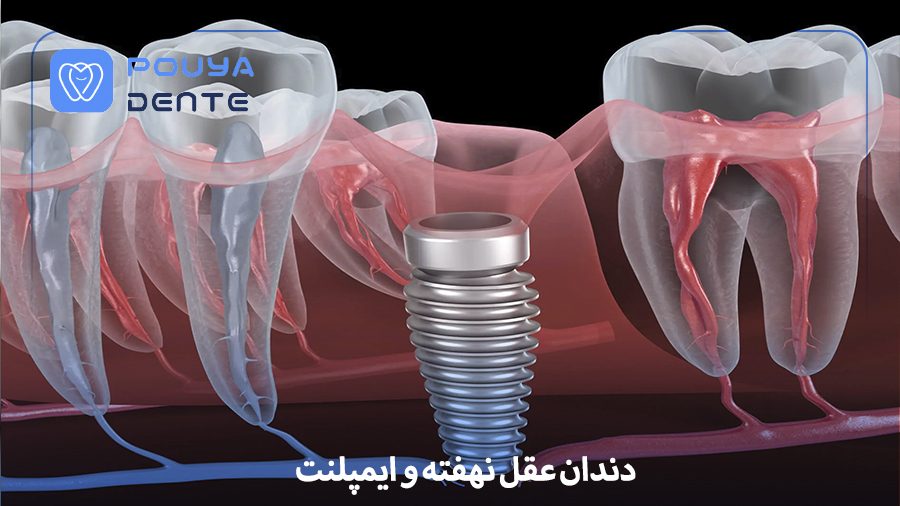

دندان عقل نهفته و ایمپلنت: جراحی با ابزارهای دقیق

در حوزه جراحی های دندانپزشکی، دو مسئله مهم که به طور مکرر مورد توجه پزشکان متخصص قرار می گیرند عبارت اند از مدیریت دندان عقل نهفته و ایمپلنت. این دو مقوله از پیچیدگی های خاصی برخوردارند که اگر با استفاده از ابزارهای دقیق و تکنولوژی های نوین انجام نشوند، می توانند نتایج درمانی ضعیف یا حتی عوارض بعدی را به دنبال داشته باشند. این مقاله به بررسی علمی و کاربردی دندان عقل نهفته و ایمپلنت، اصول جراحی، ابزارهای دقیق مورد استفاده، مزایا و چالش های مرتبط می پردازد تا دندانپزشکان و جراحان بتوانند در تصمیم گیری های درمانی خود اعتماد بیشتری داشته باشند.

دندان عقل نهفته و ایمپلنت هر دو نیازمند برنامه ریزی دقیق، بررسی های رادیولوژیک به روز، انتخاب ابزار مناسب و رویکردی علمی هستند. در حالی که دندان عقل نهفته موضوعی شایع در جمعیت های جوان تر است، ایمپلنت در بیماران میان سال و سالمند به منظور بازسازی فضای ازدست رفته دندان ها جایگاه ویژهای دارد. فارغ از تفاوت سنی یا بالینی، هر دو موقعیت پیش از هر چیز نیازمند ابزار دقیق هستند تا نتایج قابل پیشبینی و ایمن به دست آید.

دندان های عقل (مولر سوم) آخرین دندان هایی هستند که در فک رشد می کنند و به دلیل کمبود فضا، زاویه نامناسب و موانع استخوانی یا بافت نرم ممکن است در مسیر رشد طبیعی قرار نگیرند. این وضعیت بهعنوان «دندان عقل نهفته» شناخته می شود. شیوع دندان عقل نهفته بالا است و معمولاً به دلیل رویش دندان عقل در سنین ۱۷ تا ۲۵ سالگی رخ می دهد. علل نهفتگی ممکن است به دلیل موارد زیر باشد:

ایمپلنت

ایمپلنت ها بهعنوان بهترین روش جایگزینی دندان ازدست رفته شناخته می شوند. تکنولوژی ایمپلنت دندان به طور مستمر در حال پیشرفت است و به دندانپزشکان امکان می دهد نتایج بلندمدت، با ثبات و عملکردی نزدیک به دندان طبیعی ارائه دهند. ایمپلنت دندانی در شرایط زیر انجام می شود:

در بسیاری از بیماران، تصمیم گیری درباره دندان عقل نهفته و ایمپلنت به صورت مستقل انجام نمی شود، بلکه این دو موضوع می توانند به طور مستقیم یا غیرمستقیم بر یکدیگر اثر بگذارند. به ویژه در مواردی که دندان عقل نهفته باعث تحلیل استخوان، عفونت مزمن یا جا به جایی دندان های مجاور شده باشد، برنامه ریزی ایمپلنت در نواحی خلفی فک با چالش هایی همراه می شود.